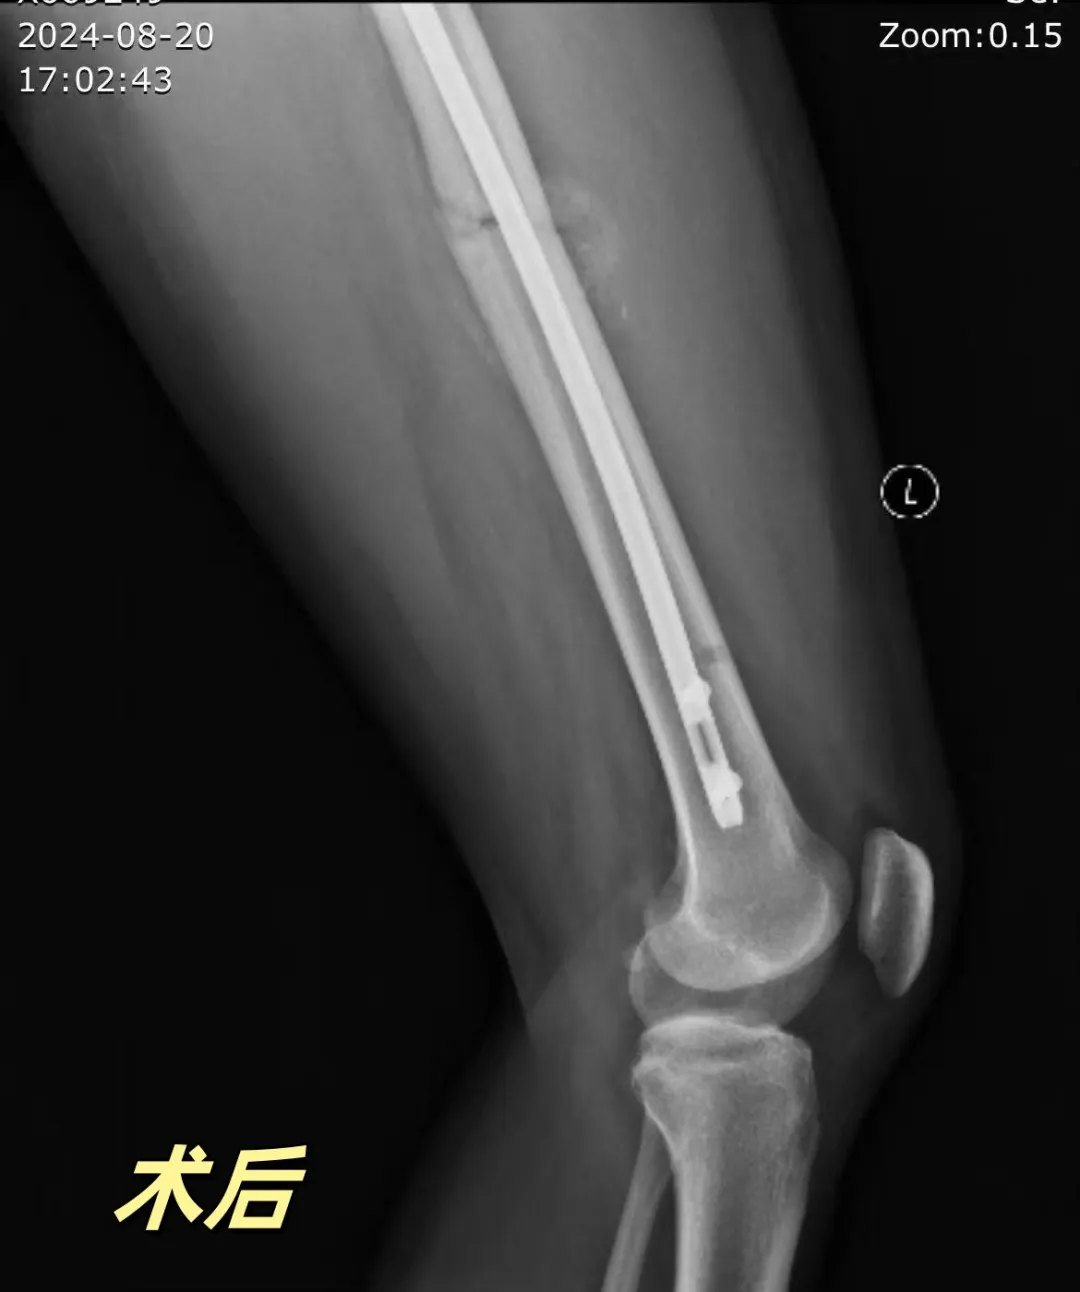

接诊这位患者后,关节外科团队认真讨论病情,考虑患者高龄,骨愈合能力差,如采取保守治疗或常规内固定治疗,患者卧床时间长易发生并发症,危及患者生命,经过充分讨论,并与患者和家属进行沟通,最终决定采用微创髓内钉手术治疗。

经过充分的术前准备,关节外科团队为戚奶奶行闭合复位髓内钉固定术,手术过程顺利。术后给予抗感染、中医床旁理疗、消肿止痛、抗凝等治疗,指导早期下肢功能锻炼。一周后戚奶奶可拄拐行走,术后复查x片显示骨折复位良好,顺利出院。